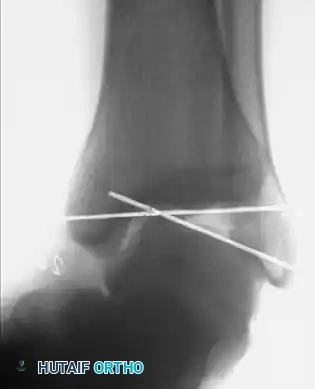

Associated Surgical & Radiographic Imaging